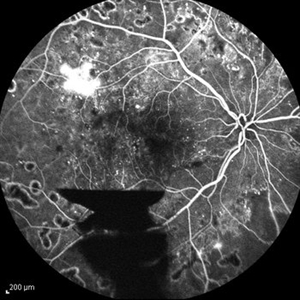

Behcet's Disease Behcet's DiseaseMar 13 2013 by Hamid Ahmadieh, MD Early phase FA of the right eye of a 23-year-old man with retinal vasculitis and branch retinal vein occlusion (BRVO) due to Behcet's disease . Photographer: Solmaz Shahmohammad, Negah Eye Center, Tehran Imaging device: Heidelberg Spectralis Condition/keywords: branch retinal vein occlusion (BRVO), retinal vasculitis

Behcet's Disease Behcet's DiseaseMar 13 2013 by Hamid Ahmadieh, MD Mid phase FA of the right eye of a 23-year-old man with retinal vasculitis and branch retinal vein occlusion (BRVO) due to Behcet's disease . Photographer: Solmaz Shahmohammad, Negah Eye Center, Tehran Imaging device: Heidelberg Spectralis Condition/keywords: branch retinal vein occlusion (BRVO), retinal vasculitis